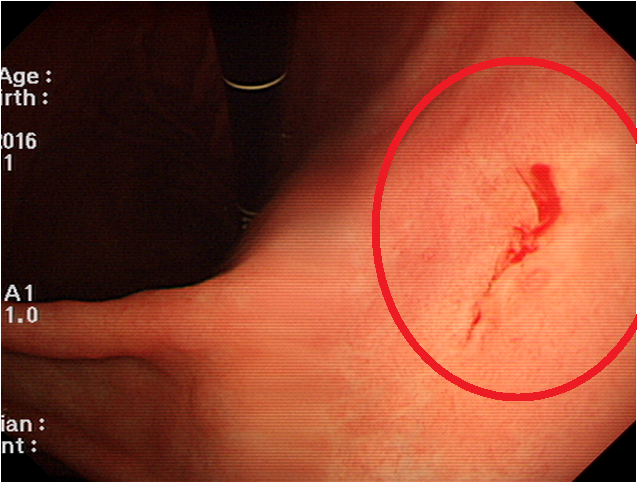

위에서 출혈이 발생하면 대변이 **검붉거나 까맣고 끈적한 형태(흑변)**로 나올 수 있습니다.

이는 위 출혈의 주요 신호이며, 위암이 진행 중일 가능성이 있으므로

한 번이라도 이런 대변을 본다면 즉시 병원을 방문해야 합니다.

심한 경우 구토 시 커피색 또는 선홍빛 피가 섞여 나오는 경우가 있습니다.

이는 위 점막이 심각하게 손상되었거나 암 덩어리로 인해 출혈이 생긴 경우이며, 즉시 응급 처치가 필요합니다.